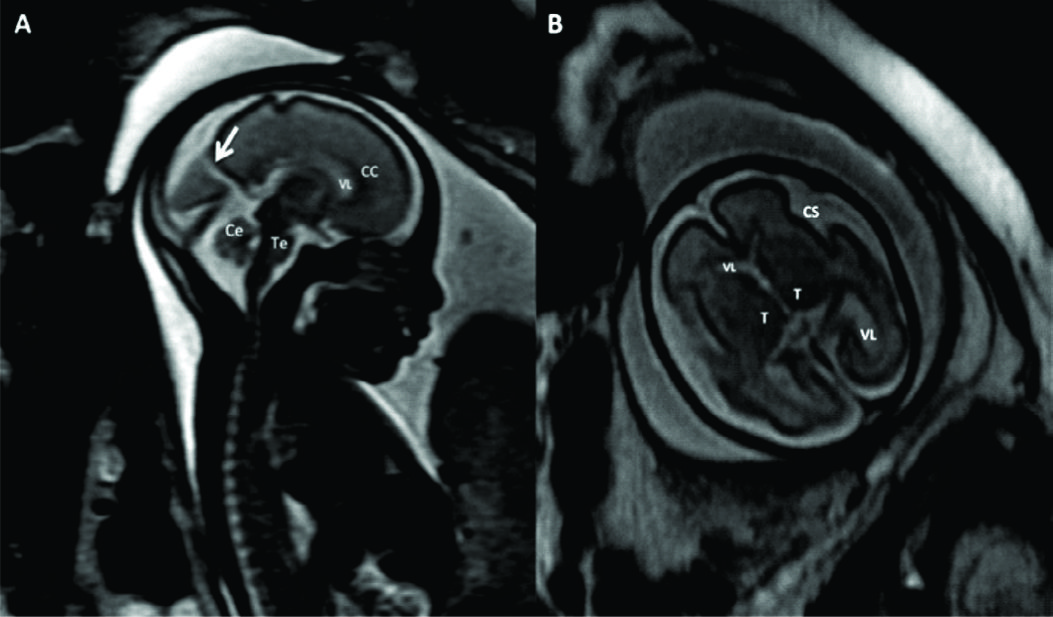

Figura 1

RM Fetal Normal (Edad Gestacional: 27 semanas).

Corte sagital en línea media (A) y corte axial a nivel bi-talámico (B) de cerebro fetal normal en la semana 27 (secuencia rápida T2). En la imagen de línea media se identifica claramente el cuerpo calloso (CC) y la cisura calcarina (è) así como también las estructuras de la fosa posterior con un desarrollo acorde.

En el plano axial se identifica la línea media y la región ganglio-basal con anatomía normal y un patrón gírico acorde a la edad gestacional con un esbozo de cisura silviana (CS).

Los diferentes sectores del sistema ventricular se identifican claramente: ventrículos laterales (VL), 3er ventrículo (situado entre ambos tálamos (T)) y IV ventrículo (situado entre el cerebelo (Ce) y tronco encefálico (Te)).